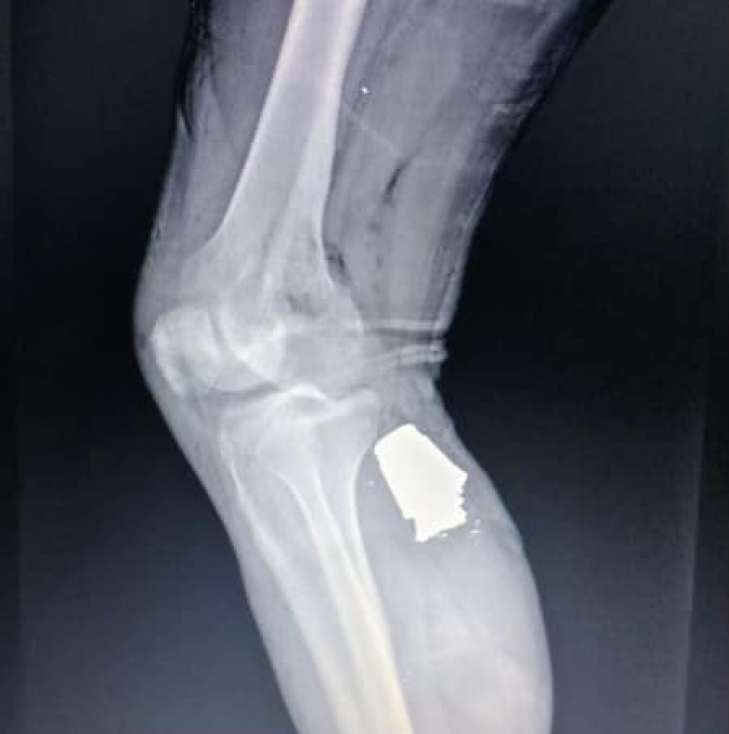

Grenade fragment stuck in Ukrainian soldier's leg

Photo: Facebook

Doctors removed a piece of a VOG-17 grenade fragment from the wounded serviceman's shin, the command of the Military Medical Clinical Centre of the Armed Forces of Ukraine reports.

The soldier's limb was saved.

The patient's condition is currently stable. He is being prepared for further medical evacuation and treatment.